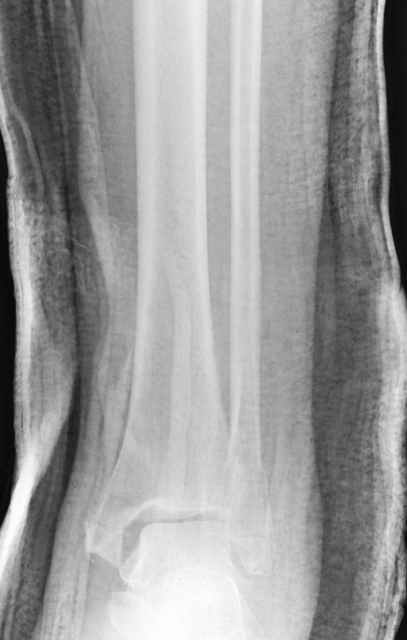

Pilon fracture:

Дистракция в аппарате или на вытяжение результат - лигаментотаксис, посмотреть бы, как сегодня расположены отломки.